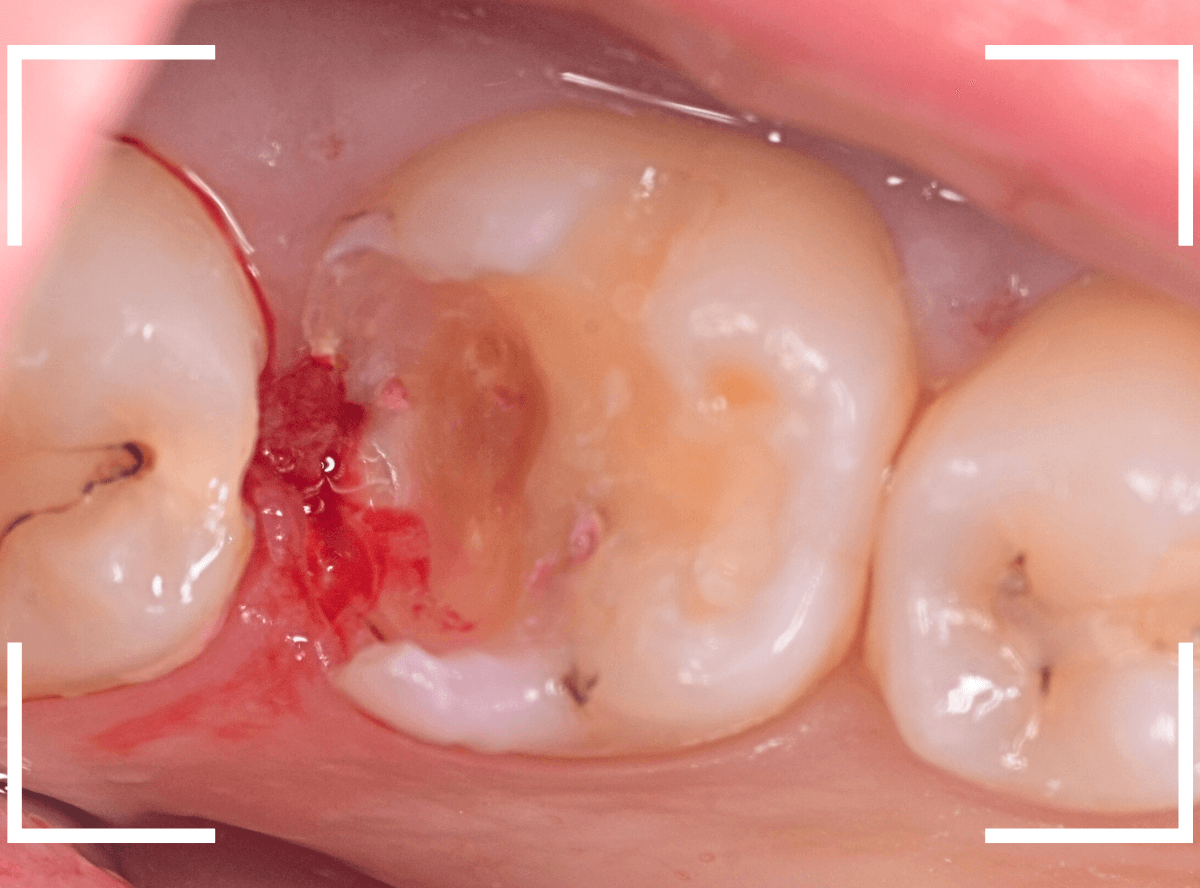

全ての虫歯を除去したところです。

幸い、後ろの歯は薄皮一枚のところで神経まで達していない虫歯ですんでいましたが、大きな虫歯だった事には変わりありません。

いつものように、神経が痛み出さないように祈りつつ、お薬で保護して経過観察します。

虫歯は症状からだけでは判断できませんが、定期受診によって、このような大きな虫歯の処置は避けられる事がほとんどです。

かならず歯科の定期受診をしてくださいね。